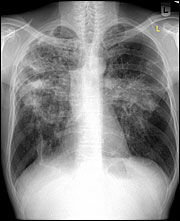

0: Lungenröntgen p.a.

thoraxu.jpg

Download Photo (386 x 390)

Datum: 09.09.2009

Betrachtungen: 46